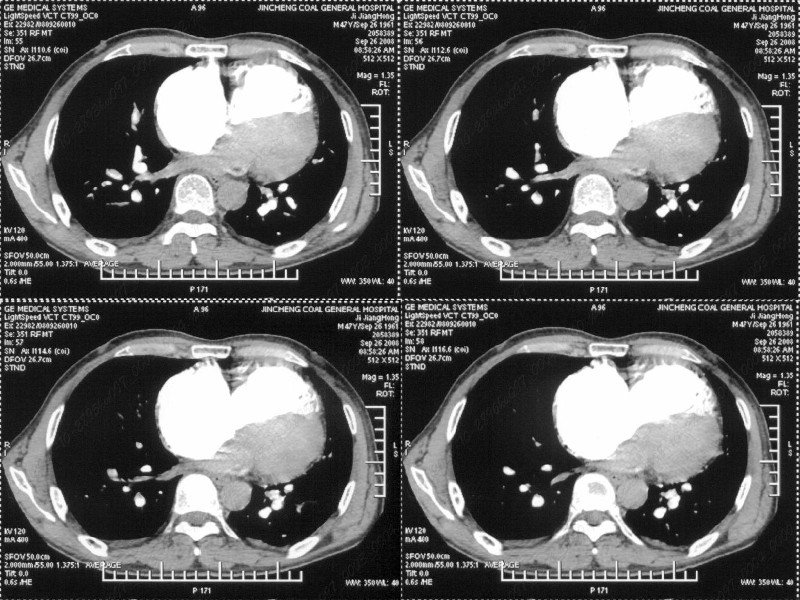

男性,47岁。胸部不适一年,ct检查发现右胸膜下结节。http://www.radida.com/bbs/forum.php?mod=viewthread&tid=46094

图像很清,资料很全。工作做的很细,向您学习!观阁下的强化图像发现,您们强化后扫描时间挺早,延迟时间大约在16—18秒之间吧。估计目的是为了观察肺动脉及分支的情况。但现有的资料并不能提示动脉栓塞改变。建议楼主可在机器上仔细观察,或许会有异常发现。另外,个人感觉右侧应为肺内结节而非胸膜结节。考虑肺内良性小结节,炎性假瘤可能性大。

病灶周围似有纤维化征像,增强明显强化,但中央可见点状低强化区,考虑慢性病变可能如炎性假瘤等,病灶边缘部分毛糙有切迹,双侧胸腔少量积液影,不除外恶性

结节未见明显强化,局部胸膜增后粘连,内缘纹理影增重伴小围星灶,局部胸膜下小三角状实变影,尖端见纤维索牵扯征,综合考虑炎性病变,有增殖表现,不出外tb灶

右肺中叶外侧段胸膜下结节状病灶,性质待定(不排除周围型肺癌可能)。

小结节的周围似乎与斜裂的走行有关,边缘分界不很清楚,与侧胸膜关系密切,有轻度强化,不能除外恶性,建议密切观察。